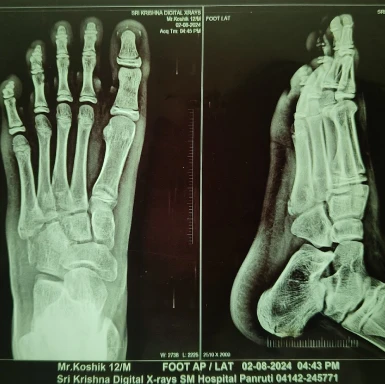

Ankle Ligament Injury Treatment in Perambur

Ankle injuries are common during running, jumping, or sudden changes in direction.

Ankle injury care includes

- Evaluation of ankle ligament damage

- Stabilization of the injured ankle joint

- Pain and swelling management

- Rehabilitation exercises for ankle strength

- Guidance for safe return to physical activity